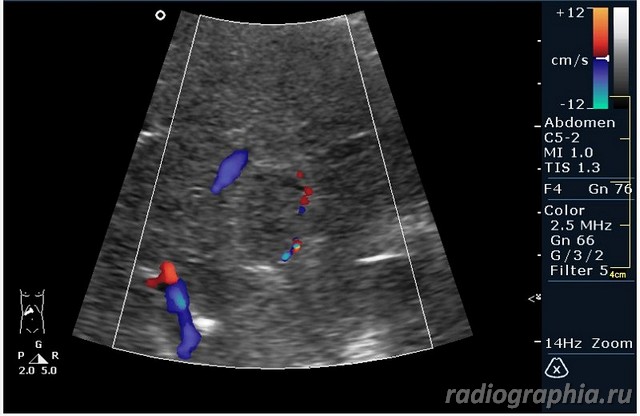

УЗИ печени. Женщина 37 лет. Жалобы на боли в эпигастрии; в печени обнаружено такое образование...

Считаю,что это опухоль,имеет неоднородную структуру,четкий контур,прорастает в сосуд(есть один такой скан) И,вообще,вся поверхность печени НЕСПОКОЙНАЯ,могут быть мелкие МТ.Интересно,что на КТ?

так и хочется назвать это метастазами но уж очень они красивые и доброжелательние по структуре (изоехогенные по отношению к структуре печени) и они больше компресирують чем проростают, склонен к ответу о доброкачественной гиперплазии. так что же на КТ?

гемангиома,рядом питающий сосуд

Мне тоже нравится версия, что это - гемангиома.Нелли писал(а):гемангиома,рядом питающий сосуд